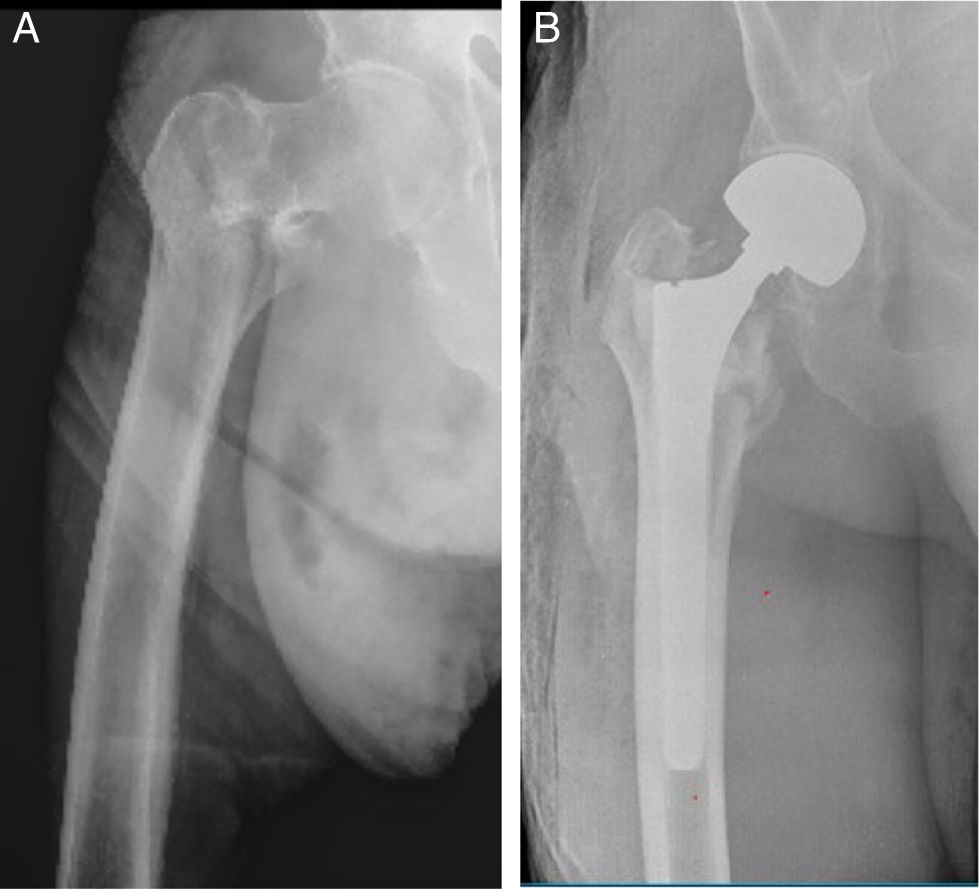

Se utilizó un vástago femoral cónico estriado no cementado de fijación distal, seleccionado de acuerdo con las características anatómicas y la calidad ósea del paciente. El vástago utilizado en este estudio, MD6® (Vincula, Río Claro, Brasil), está fabricado en aleación de titanio y presenta una superficie altamente rugosa en toda su extensión. El vástago cuenta con 8 estrías longitudinales de bordes relativamente agudos destinadas a lograr un anclaje efectivo con la cortical femoral (fig. 1). La longitud promedio del vástago fue de 180mm y en todos los casos se utilizó una cabeza femoral de 28mm junto con un componente acetabular bipolar. El fresado del canal femoral se realizó siempre de forma manual.

La alineación de los componentes fue adecuada en todos los casos (fig. 2). Se evidenció osteointegración diafisaria en las radiografías de control a los 6 meses posquirúrgicos. Se siguieron los criterios radiográficos de Engh et al.7, para evaluación de fijación de vástagos femorales no cementados evaluando ausencia de líneas radiolúcidas periimplante en zonas 2, 3, 4, 5 y 6 de Gruen, signos de remodelación ósea alrededor del vástago y confirmando la estabilidad del implante al año de la intervención. No se observaron hundimientos mayores de 5mm ni se reportó dolor femoral en ninguno de los pacientes.